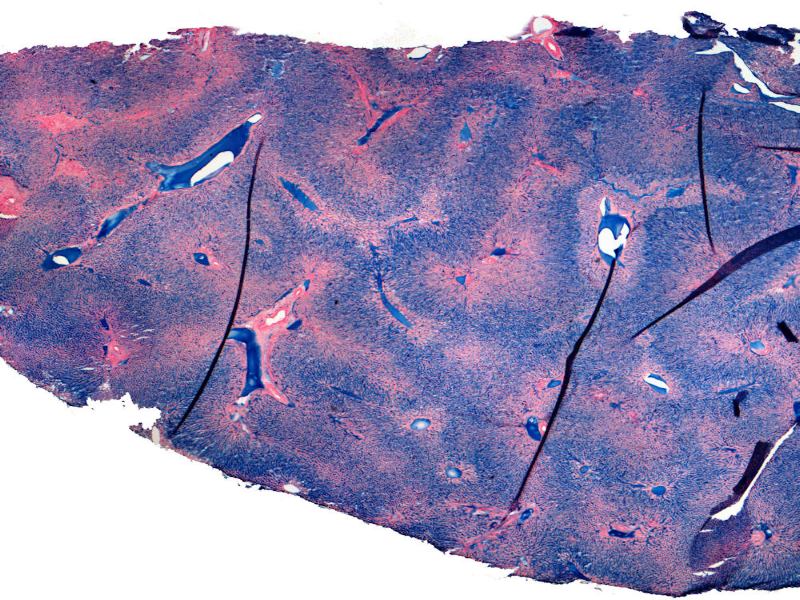

Liver Structure

3 Views of the Histology

What do we know about the liver?

This background theoretical knowledge, can be used to compare with the histological views as seen on a slide.

Compare the central vein and portal triad...

What are the clinical implications of the histological morphology?

Traumatic events in the liver

Illustrate the damaged area of Liver acinus

Visible histologically

Caused By Various Agents / Diseases

- Describe the mechanism

- Identify and explain the area

- Indicate zones of damage on a sketch

- Correlate with slide